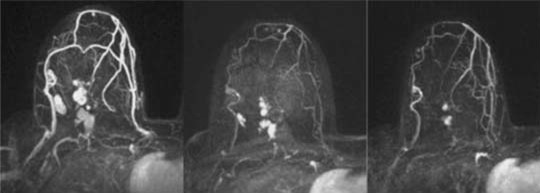

SV-BR-1-GM是一种现成的通用型肿瘤全细胞治疗疫苗。在SV-BR-1-GM的I期单臂试点研究中,有75%的患者总生存期均超过33个月。其中患者A002患有转移性乳腺癌,病灶累及乳腺、肺部、软组织和骨骼,且对化疗药物、放疗及抗激素治疗均产生耐药。在SV-BR-1-GM治疗两个月后,其先前增大的肺部病灶完全消退,五个...